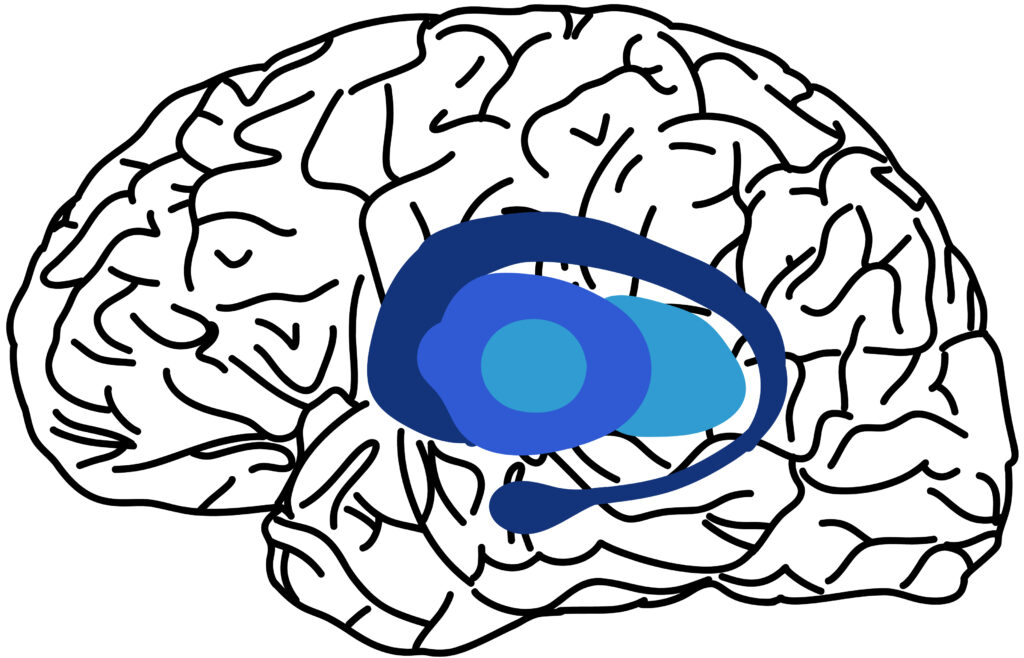

Los ganglios basales se localizan en la profundidad del cerebro, rodeando el tálamo y la parte anterior del mesencéfalo. Además, forman parte del sistema motor extrapiramidal y trabajan en conjunto con el sistema piramidal y límbico. Anatómicamente, podemos afirmar esta compuesto por las siguientes partes: cuerpo estriado, la substancia negra, el globo pálido y el núcleo subtalámico.

En primer lugar, el cuerpo estriado, una estructura compleja formada por el núcleo caudado y el putamen, destaca por ser la principal vía de entrada de información a los ganglios basales. Por otro lado, en lo que respecta al globo pálido y el núcleo subtalámico, constituyen la vía principal para la salida de la información. Así, ambos trabajan en conjunto para regular los movimientos del cuerpo a través de la inhibición de la actividad motora.

Por último, referido a la substancia negra, esta se divide en dos regiones distintas: la substancia negra compacta y la substancia negra reticular. La primera de ellas, es conocida por su papel principal en la producción de dopamina que controla los movimientos y el estado de ánimo. Por otro lado, la substancia negra reticular, se encuentra involucrada en la regulación de patrones motores y la modulación de las vías motoras (Lanciego et al., 2012).